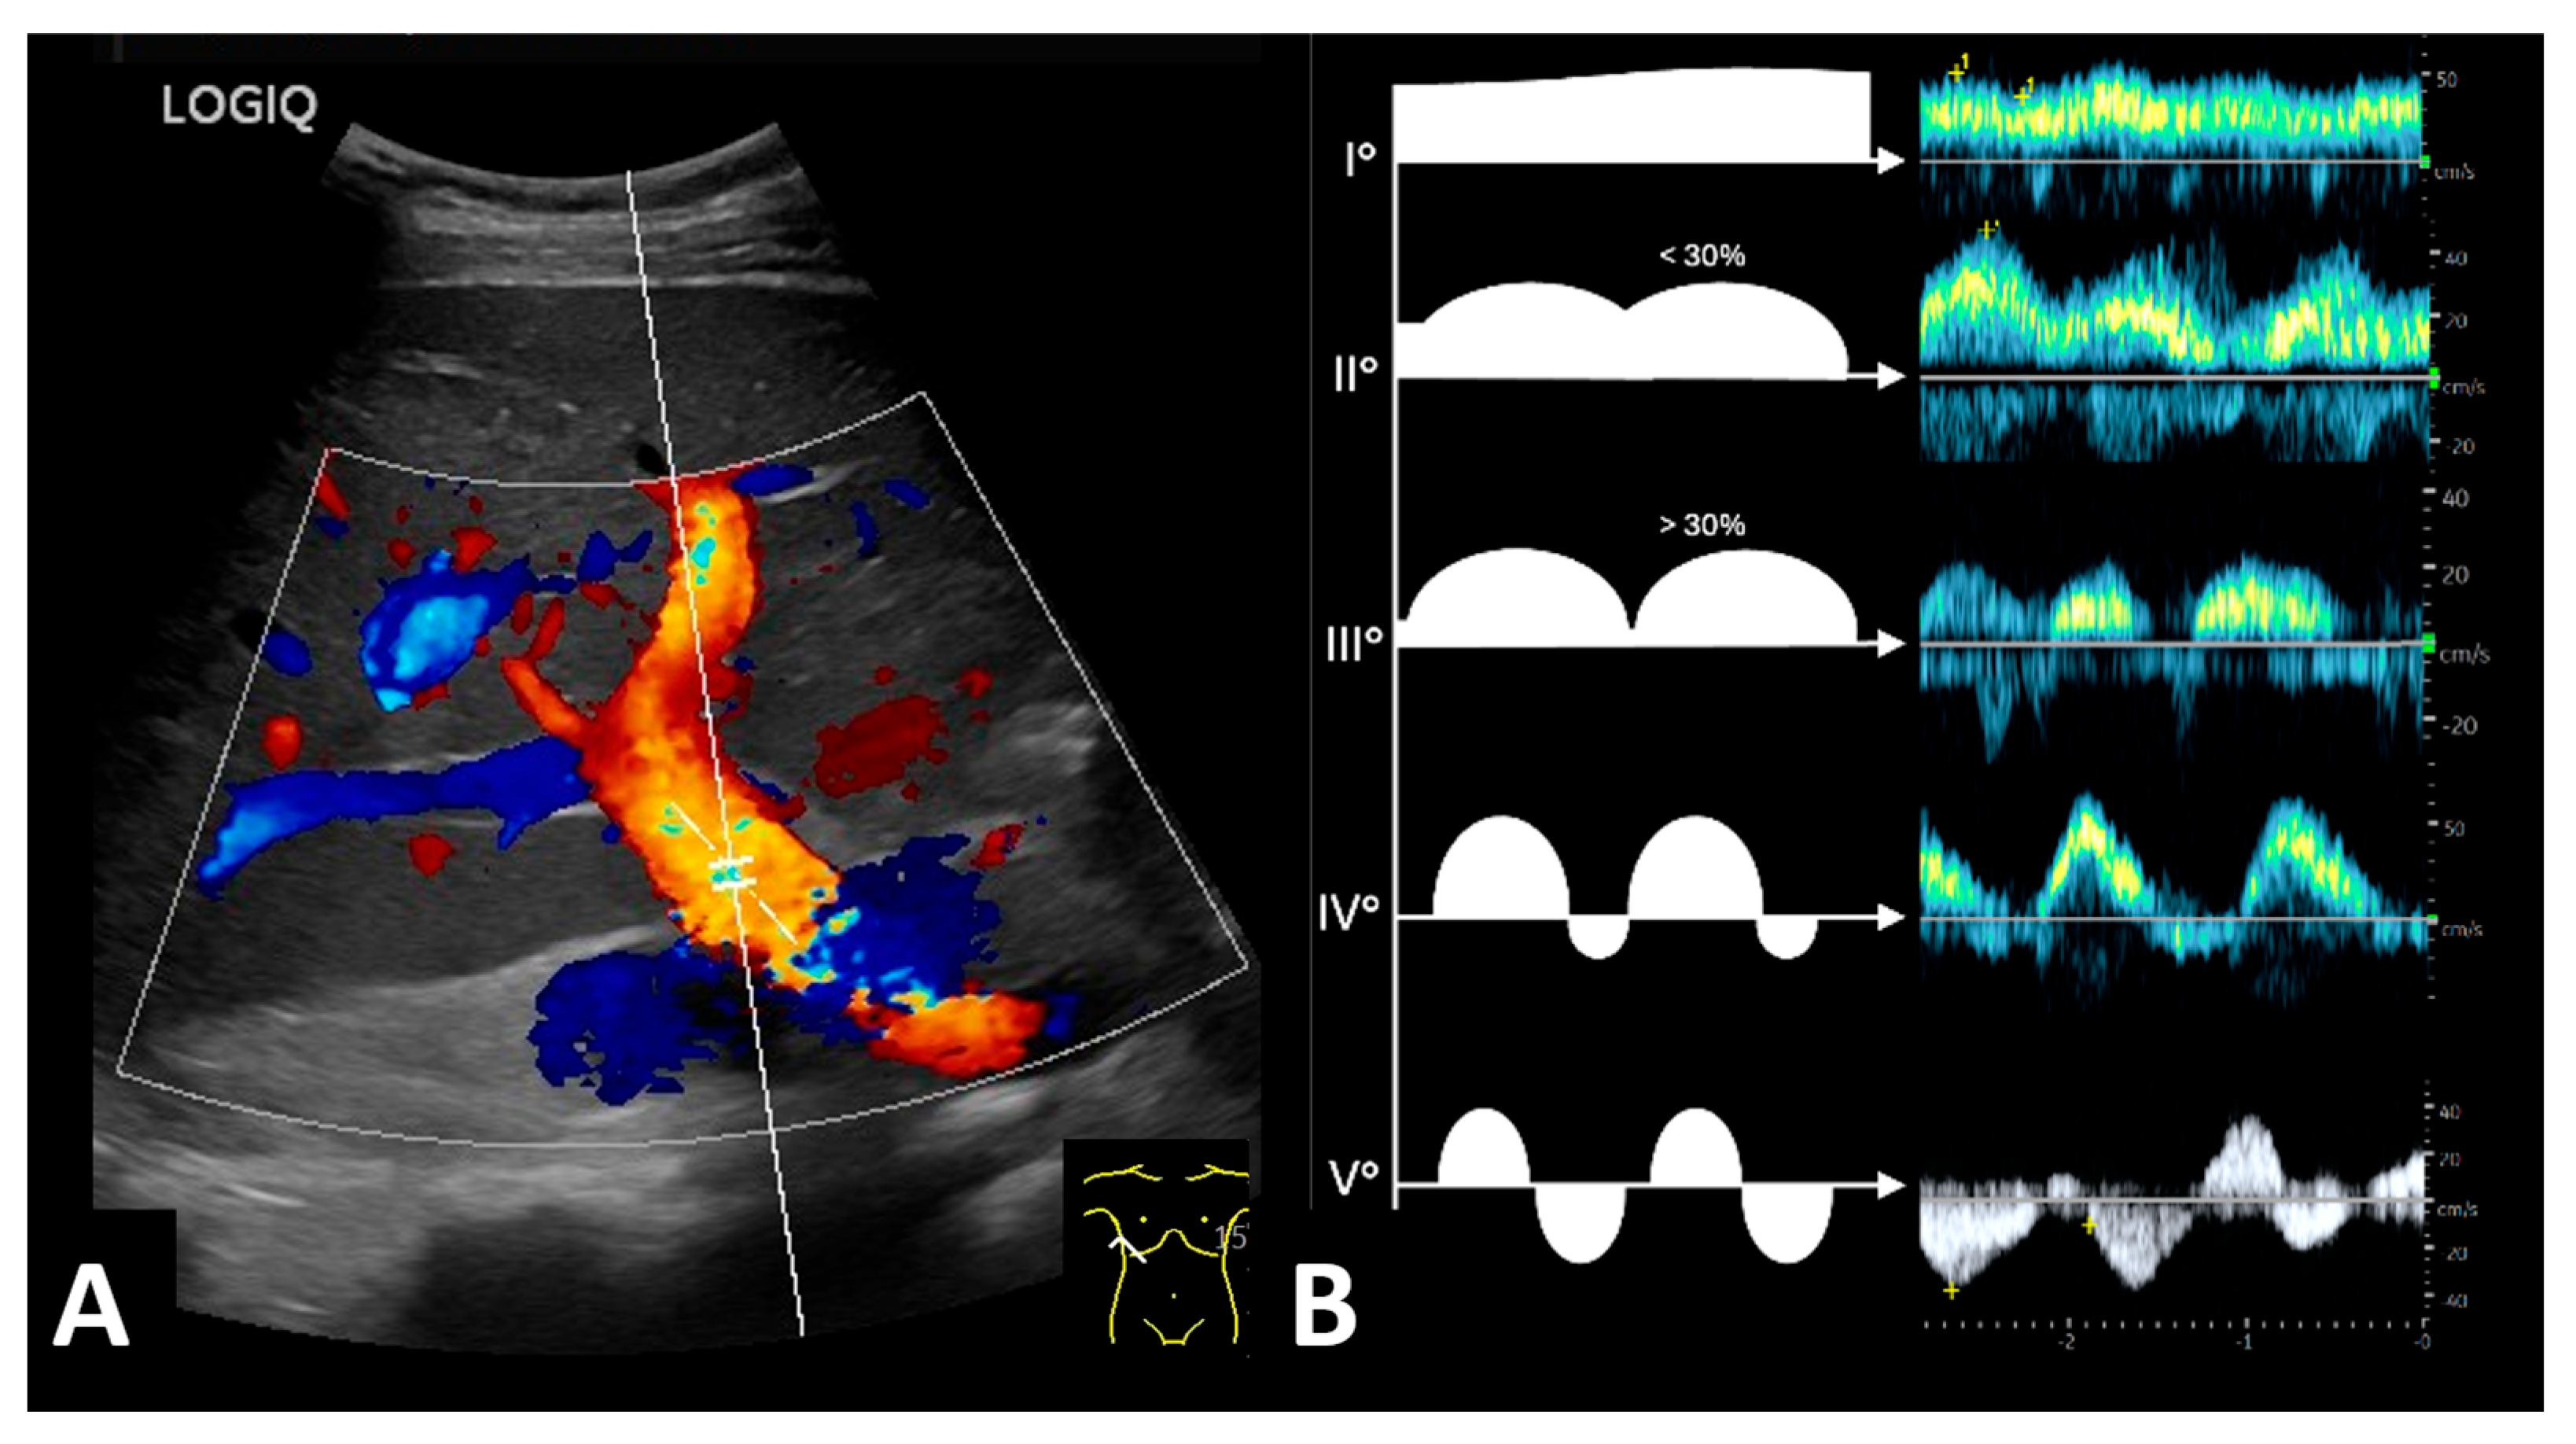

3.4. Pre-Transplant Liver Doppler Sonography Identifies Patients at Risk for Cardiorenal Syndrome

| Evidence of venous congestion in liver duplex sonography (%) | 22.9 (8/35) | 7.4 (2/27) | 75.0 (6/8) | p ≤ 0.001, φ = 0.68 |